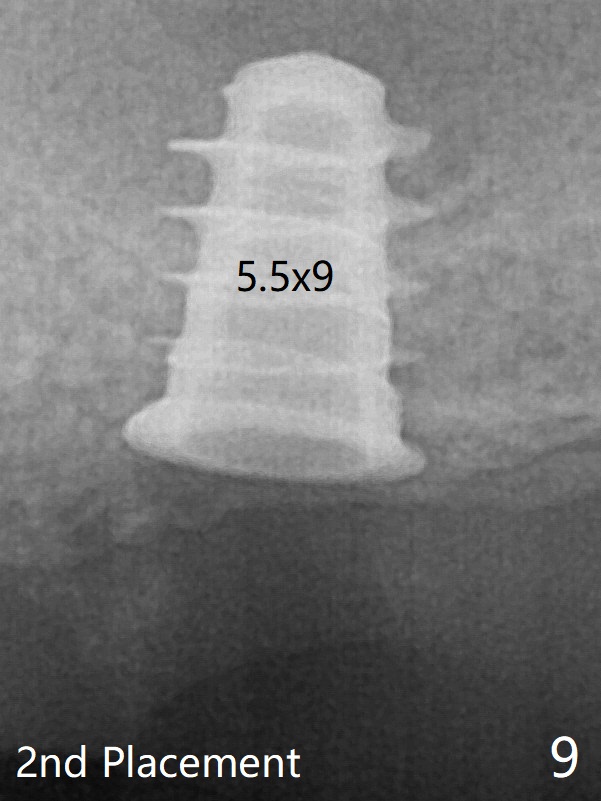

The implant is stable upon uncover 3.5 months postop (Fig.11).  Progressive loading will be next.